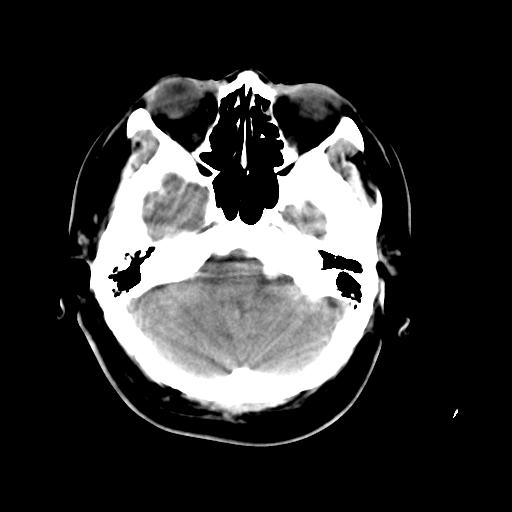

以下是引用liuyue在2008-4-28 13:34:00的发言:[br]右额叶条状高密度影,边缘清楚,周围未见水肿及占位.[br]考虑:血管畸形可能性大.[br]建议:强化ct扫描或mri检查.除外脑回钙化.

以下是引用论黑辩白在2008-4-28 12:53:00的发言:[br]右额叶局限性脑萎缩,右额叶见条状高密度影,建议mri进一步检查。[br][br][本贴已被 论黑辩白 于 2008-4-28 13:08:16 修改过]